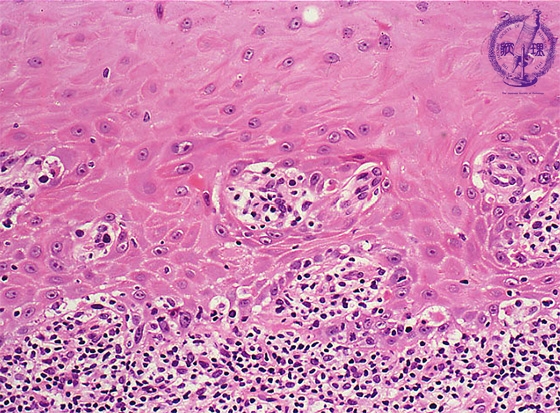

Microscopic finding (HE stain, high-power view):The basal cells show vacuolar change, or hydropic (liquefaction) degeneration (black arrows) and there is cleft formation between the epidermis and papillary dermis. Colloid bodies (degenerating keratinocytes) (red arrow) are seen in the epithelium.